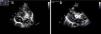

A male neonate was born at term. Obstetric ultrasound at 36 weeks showed two hyperechogenic masses, one located in the mid interventricular septum occupying the total thickness of the septum and the other attached to the anterior leaflet of the mitral valve. The baby was born by normal delivery, with a birth weight of 3280 g and an Apgar score of 10 at first minute and 10 at fifth minute. On physical examination, he had a grade III/VI systolic heart murmur best heard at the left sternal edge. An echocardiogram on day one revealed multiple masses with features of rhabdomyomas, located at the apex of the right ventricle, tricuspid and mitral valves, interventricular septum, left ventricular lateral wall and outflow tract. The left ventricular outflow tract mass (15 mm×9 mm) caused a peak gradient of 92 mmHg and a mean gradient of 49 mmHg (Figure 1a and b). The newborn underwent serial clinical and echocardiographic assessment. He remained asymptomatic and the masses underwent progressive reduction. At one month the left ventricular outflow tract mass measured 14 mm×8 mm and at latest follow-up at six months measured 12 mm×8 mm (Figure 2a and b). The peak left ventricle-aorta gradient had decreased to 29 mmHg, with a mean of 13 mmHg, at the last follow-up. A diagnosis of tuberous sclerosis was made by genetic testing, which confirmed a mutation in the TSC-2 gene.

(a) Day one, apical 5-chamber view: a large mass obstructing the left ventricular outflow tract, measuring 15 mm×9 mm; (b) day one, parasternal long-axis view: a large mass almost completely occluding the left ventricular outflow tract. Ao: aorta; LA: left atrium; LV: left ventricle; RA: right atrium; RV: right ventricle.